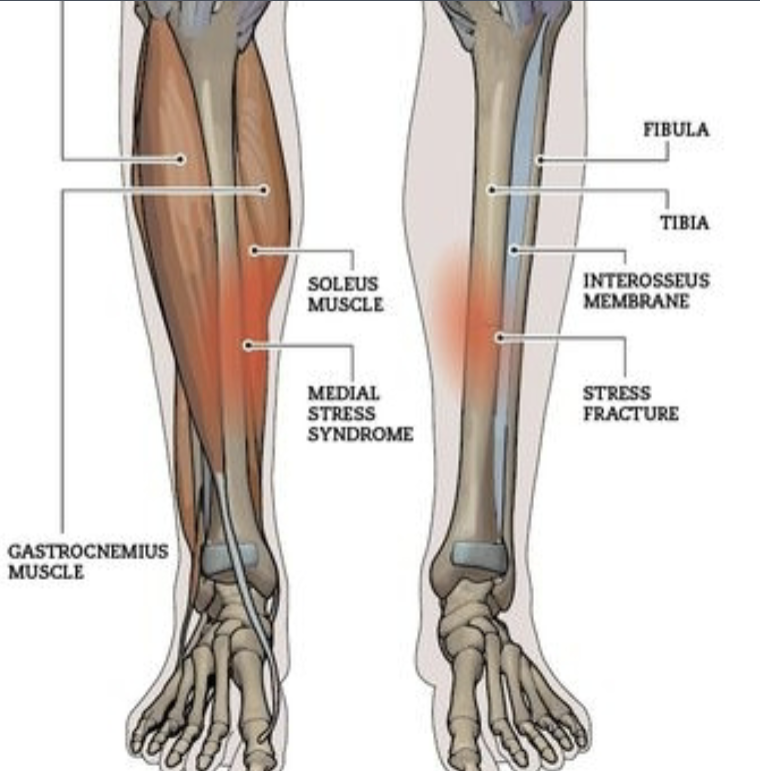

What is the medical term for “shin splints”? What is the MOI and predisposing factors that can lead to shin splints?

Medical term is Medial Tibial Stress Syndrome, due to any muscles attached to Tibia pulling on periosteum from Tibia, is a precursor of tibial stress fractures

MOI: repetitive stress like running and jumping

Predisposing factors: overtraining, flat feet, poor footwear